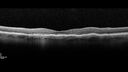

78 year old female No visual complaints referred for evaluation

Medical Hx: Rheumatoid Arthritis. Atrial Fibrillation. Benign Intracranial Hypertension. Sjogrens Syndrome. Osteoporosis.

Systemic Meds: PLAQUENIL (Stopped 2 months ago). Leflunomide. Lidocaine. Gabapentin. Vitamin D. Multaq. DILTIAZEM.

1993 Plaquenil Initially 400 mg /day (9 mg/kg/day x 18 years) then 2011 200 mg daily - (4.6 mg/kg/day x 10 years) STOPPED 3/2021

The patient weighs 100 lbs and is 4’ 2†tall - Images are from 3/2021 and 5/2022

There was no progression 1 year after stopping plaquenil in this patient.